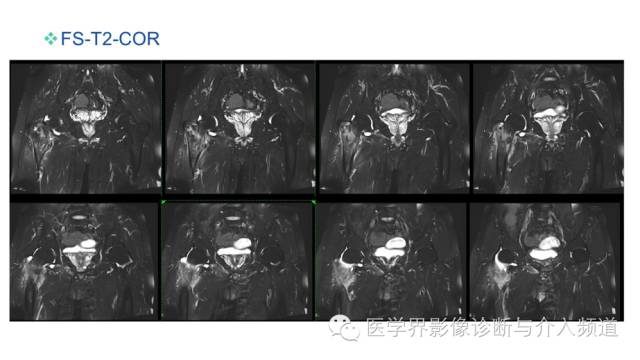

• 【PPT】臀中肌及臀小肌肌腱撕裂

【PPT】臀中肌及臀小肌肌腱撕裂